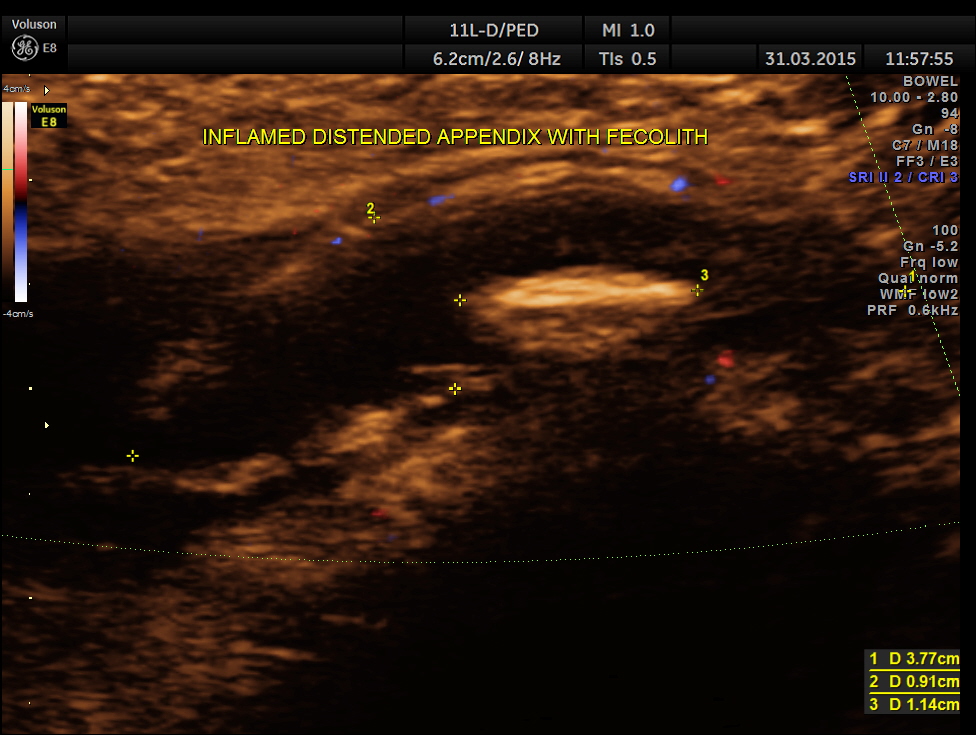

Now this looks more like an inflamed appendix with a prominent fecolith of size 11.4 mms , throwing a shadow.

The following pictures are with a high resolution probe.

The following picture shows the long and short axis views.

Careful attempt to establish any continuity of the dilated ” tube ” to the ureter or dilated pelvis , showed that the dilated structure was separate from the right ureter .

A diagnosis of Acute appendicitis with fecolith was made . CT scan of the abdomen confirmed the diagnosis and after surgery the patient is doing well.

This patient had some misleading signs and symptoms . It is always better to establish the ” connection” between the dilated ureter and the kidney. Usually appendix is picked up better with high resolution transducers. But in this patient , it was well picked up with a routine abdominal transducer. The colour doppler was useful in this patient also.